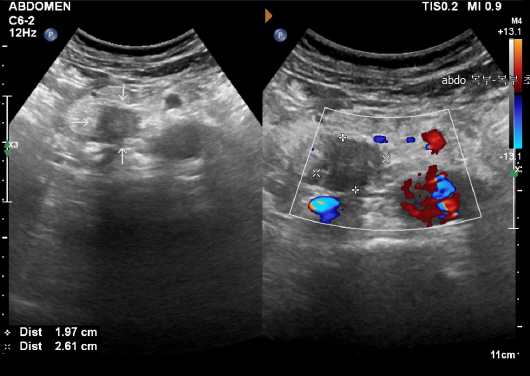

신장 질환

신장은 인체의 대사 노폐물을 제거하고 수분 및 전해질 균형을 유지하는 중요한 역할을 합니다. 신장에 문제가 발생하면 체내의 여러 기능이 부정적인 영향을 받을 수 있습니다. 복부 CT는 신장 결석, 신장 종양 및 기타 신장 관련 질환을 진단하는 데 도움을 줍니다.

신장 결석: 예방법과 치료 방법

신장 결석은 신장에서 형성된 경결된 물질로, 통증을 유발할 수 있습니다. 복부 CT는 결석의 위치와 크기를 정확하게 파악할 수 있으며, 이 정보를 바탕으로 적절한 치료 방법을 결정하는 데 매우 중요합니다. 결석이 발견되면, 물리치료, 약물 치료, 혹은 필요 시 수술이 고려될 수 있습니다. 신장 결석은 수분 보충과 균형 잡힌 식사를 통해 예방할 수 있으므로, 생활 방식의 변화 또한 동반되어야 합니다.